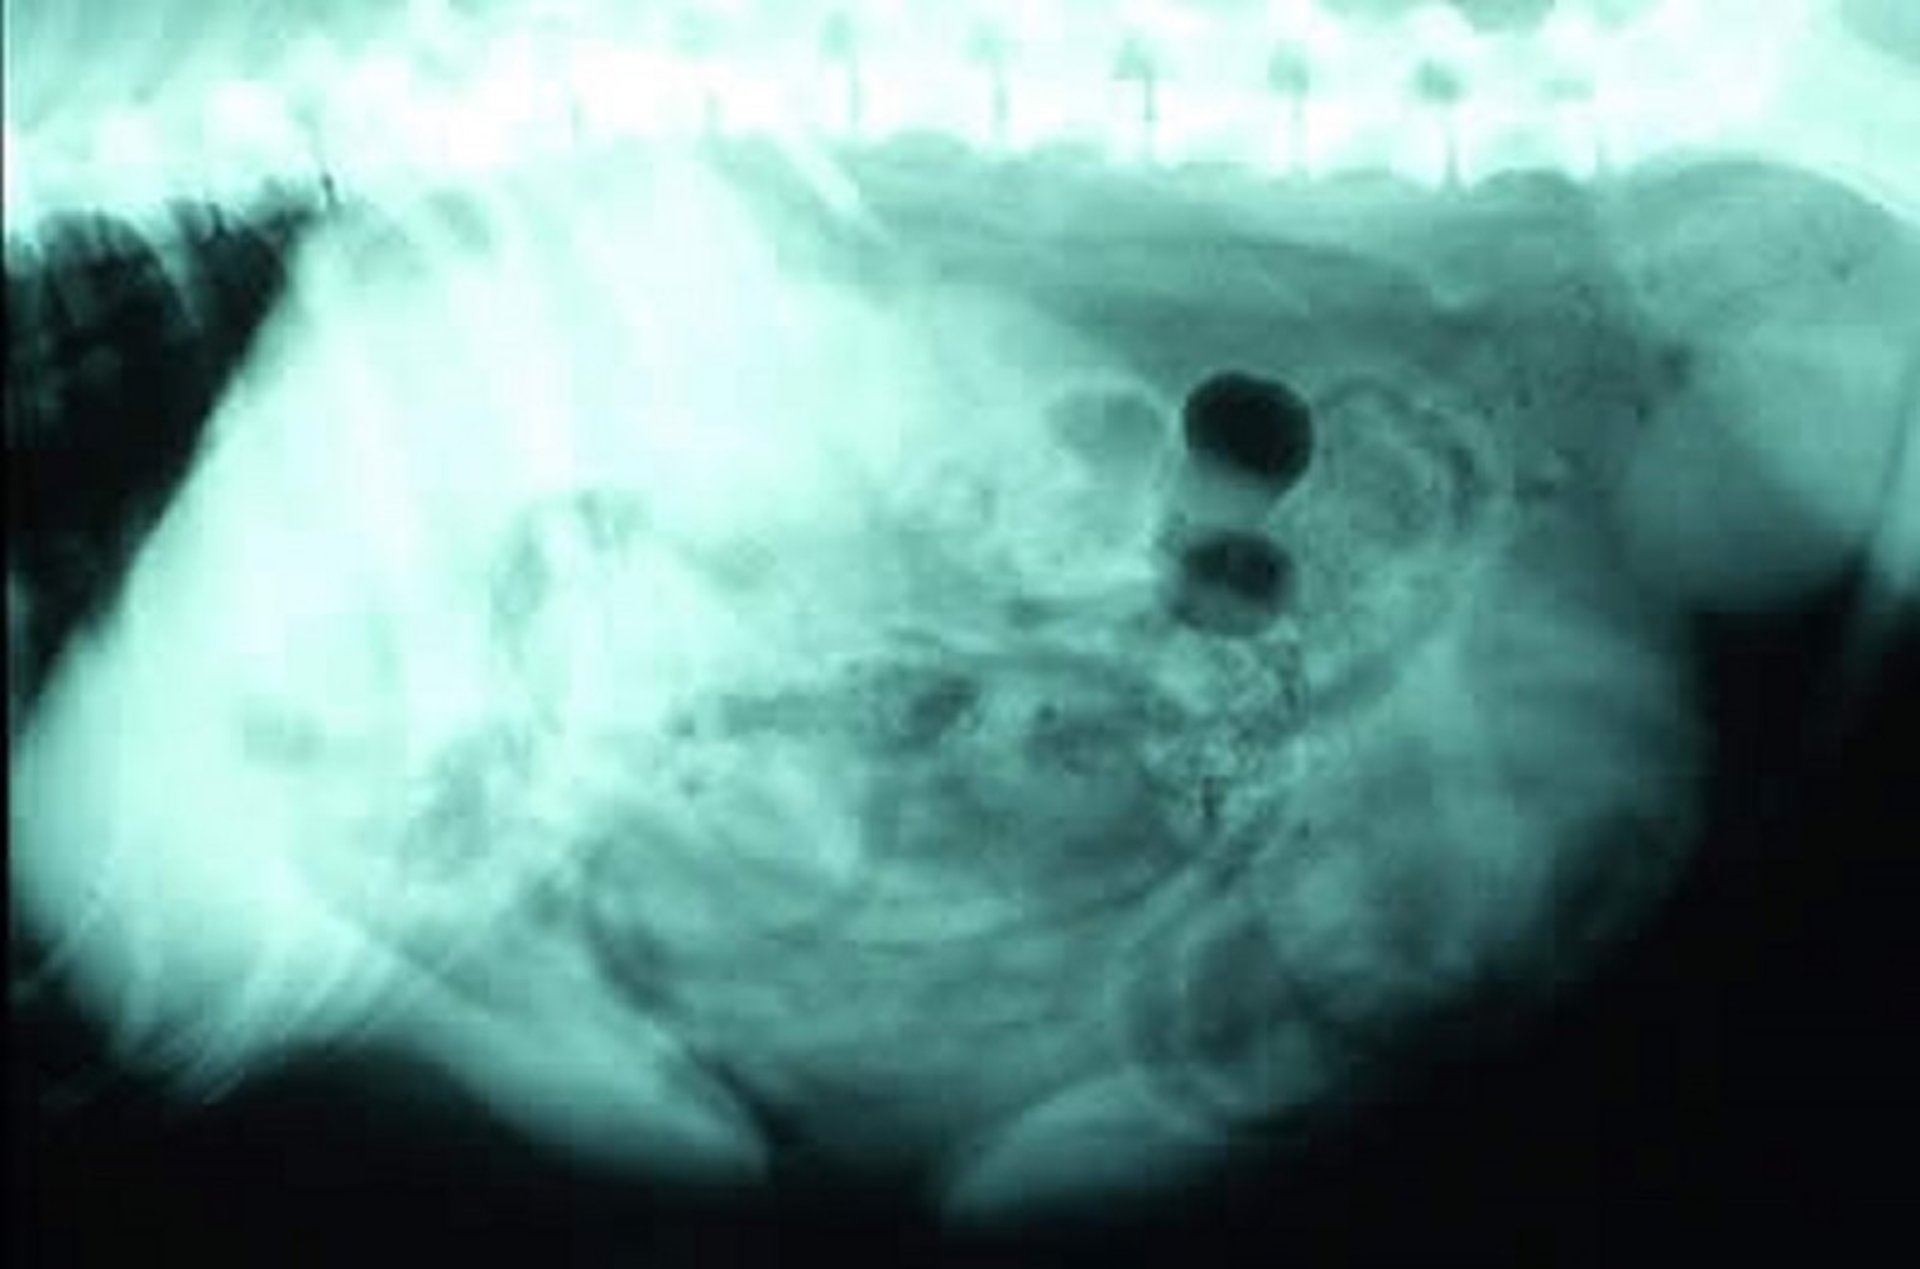

Prostatomegaly, radiograph, dog

Lateral radiographic view in a dog with prostatomegaly. In the caudal ventral abdomen, the enlarged prostate appears caudal to the bladder and is approximately half the size of the bladder with a similar radiographic density and shape (giving the illusion of a double bladder).

Courtesy of Dr. Ronald Green.